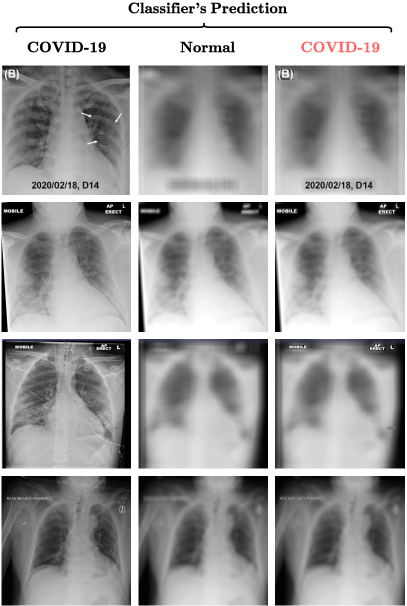

Figure. 6 showcases further examples of our visualization method giving insights to the underlying decision making process of the classifier and potentially debuging and improving it. It can be seen that the iGOS++ visualizations (second column) are highly weighting in the text region in the images, i.e. the letter ”R”. The third column shows images when only a small fraction of the pixels (e.g. 6%), referred to as Pixel Ratio (PR), were inserted back into the baseline image (a Gaussian-blurred of the original image). However, these small amount of pixels, which mostly include the text region, are predicted as COVID-19 classes with their corresponding confidence (shown in green color). On the other hand, using the same iGOS++ visualizations, when only a small fraction of the pixels (e.g. PR: 12%) are removed from the original image, the classifier shows different predictions (than COVID-19). The corresponding confidence (shown in red color) is depicted on the top of the perturbed images. It should be noted that this confidence is not high enough so that the images get classify as COVID-19.

Refer to caption

Figure 6. Showcase for capability of the iGOS++ in detecting bugs in a COVID-19 classification pipeline. The X-ray images in the first column belong to COVID-19 patients. The second column shows iGOS++ visualizations at 32×\times32 resolution where our method highlights the text region, the letter ”R”. The third column shows images when only a small fraction of the pixels (e.g. 6%), referred to as Pixel Ratio (PR), are inserted back into the baseline. Interestingly, the insertion of these small amount of pixels, which mostly include the text region, is enough for the perturbed images to be classified as COVID-19 (The corresponding confidence scores are shown in color green). The fourth column shows the opposite scenario where only a small fraction of the pixels (e.g. PR: 12%) are removed (blurred) from the original image and that is enough for the perturbed images to be mis-classified, i.e. not COVID-19. Obviously, the confidence score for these images (shown in color red) are lower than of Normal or Pneumonia classes.